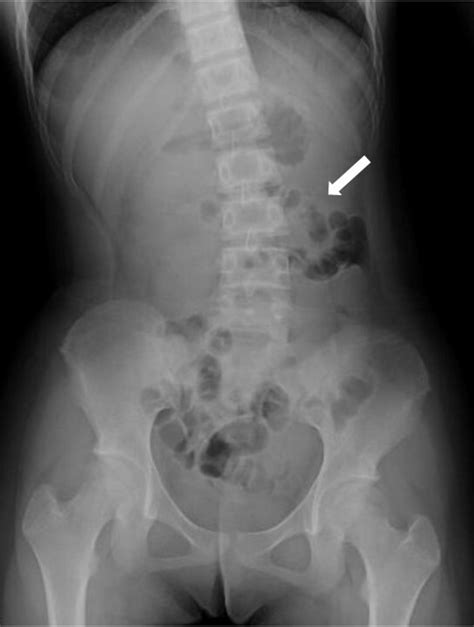

Abdominal X-ray Can show radiolucent areas along the bowel wall, but lacks sensitivity.

When reviewing imaging, radiologists look for the specific appearance of "bubbly" gas collections along the serosal or submucosal surfaces. Differentiating these cysts from free air (pneumoperitoneum) is the most critical step for the radiologist to ensure the patient is not facing a surgical emergency.